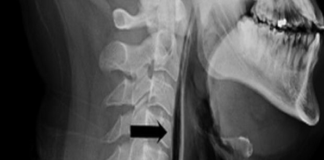

Bir İngilizin hapşırığını tutmaya çalışması nefes borusunda delik açılmasına neden oldu.

Uzmanlar bu tür bir yaralanmanın dünyada bir ilk olduğuna inanıyor.